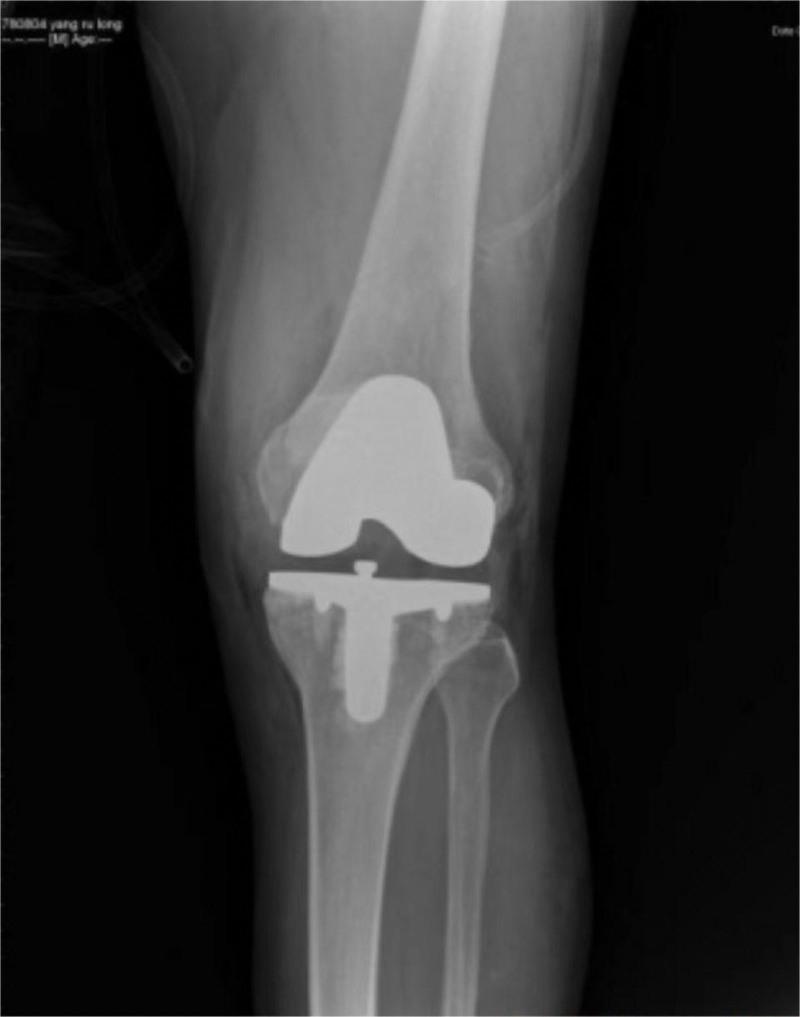

An elderly male aged 67, was admitted to the hospital for chronic pain in his left knee. An outpatient physical examination reveals a significantly thicker left lower limb accompanied by multiple varicose veins. The right lower limb was 2 cm short on the opposite side, and the right foot was stunted with high arch deformity. The entire body was covered in a red grape globus, which faded after pressing. He was diagnosed with KTS. We performed TKA for him after blood coagulation examination. The patient recovered well after the operation. He was followed up for 1 year, The patient is in good condition and satisfied with the operation.

一名 67 岁老年男性,因左膝慢性疼痛入院。门诊体检发现左下肢明显增粗,伴多发静脉曲张。对侧下肢短缩 2cm,右足发育不良,高弓畸形。全身布满红色葡萄样斑,按压后褪色。诊断为 KTS。行凝血检查后为他行 TKA。术后患者恢复良好。随访 1 年,患者情况良好,对手术满意。